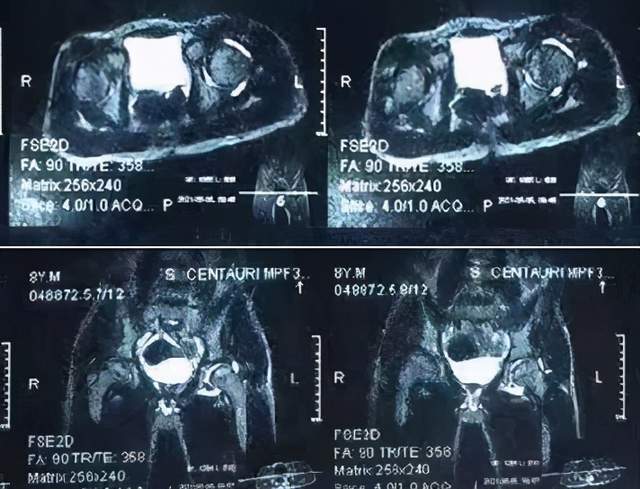

这是髋关节一过性滑膜炎?

小儿髋关节滑膜炎,多次复发,终于治好了,一路都是泪(二)(第2页)